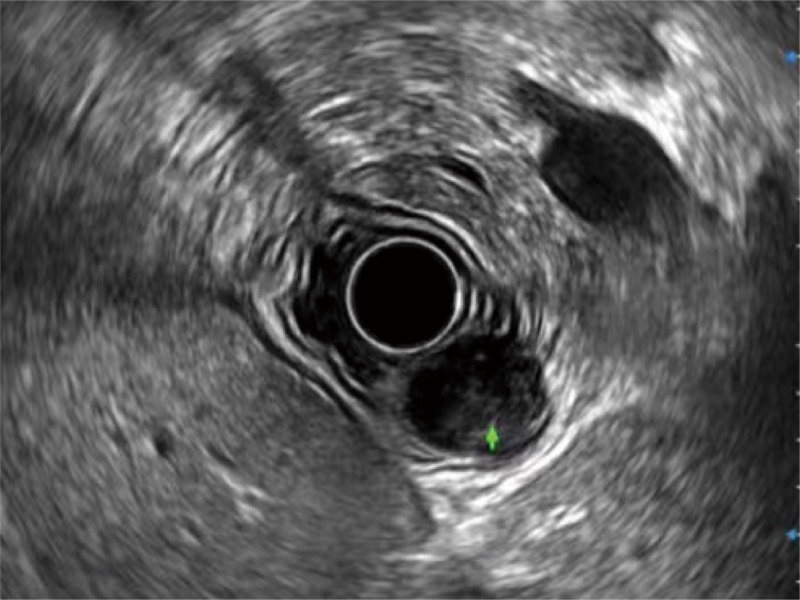

食管内间质瘤清晰显像

360°电子环形扫查与高清内镜影像相结合,提供了良好的插入性能和高清的内镜图像

卓越的宽频设计,满足医生探查不同深度的组织和器官